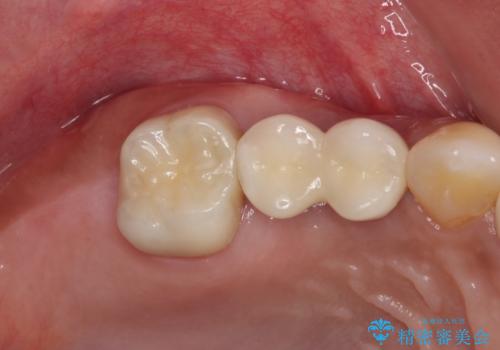

破折した歯を抜去し、インプラントによる補綴を行うこととしました。

銀歯の下のむし歯については、優先度の高い方からセラミッククラウンなどで治療していくこととしました。